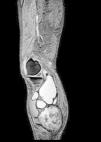

Paciente varón de 83 años, con artrosis, que acude a urgencias por cuadro agudo inflamatorio de la pierna que simula trombosis venosa profunda. En la exploración física se palpa gran masa de consistencia elástica, no pulsátil, dolorosa, en el hueco poplíteo, que se extiende hacia la pierna (fig. 1). Se plantea el diagnóstico diferencial con quiste de Baker. Se practica, como técnica de elección, una ecografía. El modo Doppler-color muestra permeabilidad del sistema venoso profundo. La ecografía musculoesquelética evidencia colección bien definida, adyacente al vientre medial del músculo gastrocnémico, llena de ecos difusos, predominantemente de baja amplitud (fig. 2). A pesar de no ser un aspecto infrecuente, las dimensiones de la tumoración hacen que la ecografía no resulte suficiente y se decide realizar RM específica de rodilla con secuencias potenciadas en T1, secuencias T2* (figs. 3–5) y tras la administración de contraste por vía intravenosa, confirmando la existencia de quiste de poplíteo gigante de 17×9cm. El paciente es tratado de forma conservadora, pautando en primer lugar antiinflamatorios no esteroideos, mejorando clínicamente y encontrándose actualmente asintomático, transcurridos los 6 primeros meses. Por dicho motivo, junto con la edad del paciente y a pesar de que el quiste apenas ha modificado su tamaño, se desestima, de momento, tratamiento quirúrgico.